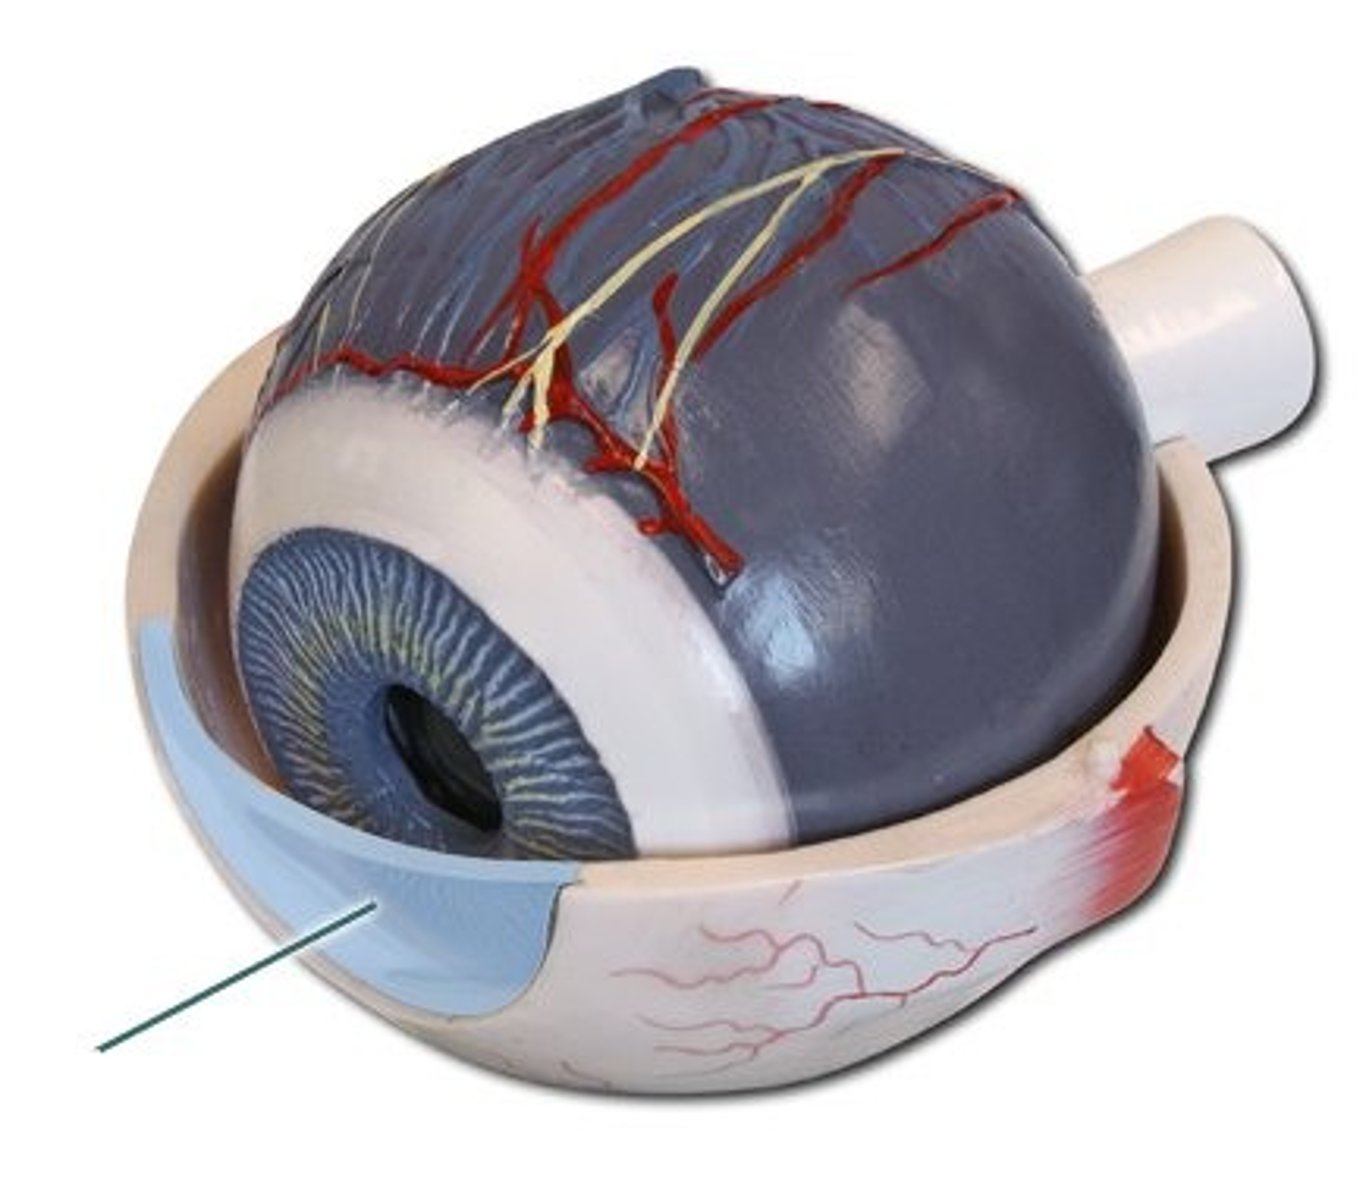

Cornea

eye's clear protective outer layer covering the pupil and iris

Pupil

small adjustable opening in the center of the eye through which light passes

Iris

a ring of muscle tissue that forms the colored portion of the eye around the pupil and controls the size of the pupil

Retina

the light sensitive inner surface of the eye, containing the receptor rods and cones

Rods

retinal photoreceptors that detect black, white, and gray and are sensitive to movement

Cones

retinal photoreceptors that are concentrated near the center of the retina and function in daylight or in well-lit conditions

Blind spot

the point at which the optic nerve leaves the eye, creating a "blind" spot because no receptor cells (rods or cones) are located there